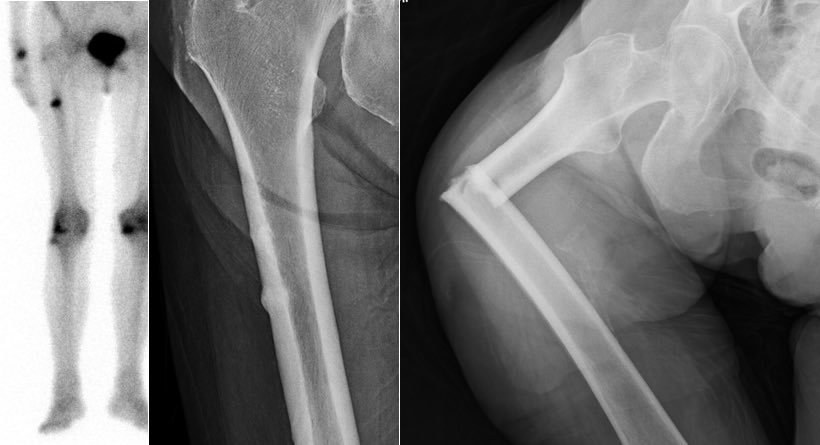

-أثبتت الدراسات أن وجود كسر بسبب الهشاشة هو أقوى دليل لإحتمال وقوع كسر آخر مع أدنى إصابة أو حركة خفيفة.

مضاعفاته:قد يسبب تنخر العظم في الفك أو حدوث كسر غير عادي في أعلى عظمة الفخذ.

الخلاصة:ينبغي أخذ أدوية الهشاشه في حال وجودها والمضاعفات التي ذكرتها نادرة والفائدة تفوق تركها.في حال حدوث كسر غير عادي في عظمة الفخذ يلجأ الجراح إلى إيقاف البييفوسوفيت فورا وسيقوم بتثبيت عظمة الفخذ سواءا كان الكسر كامل أو جزئي.